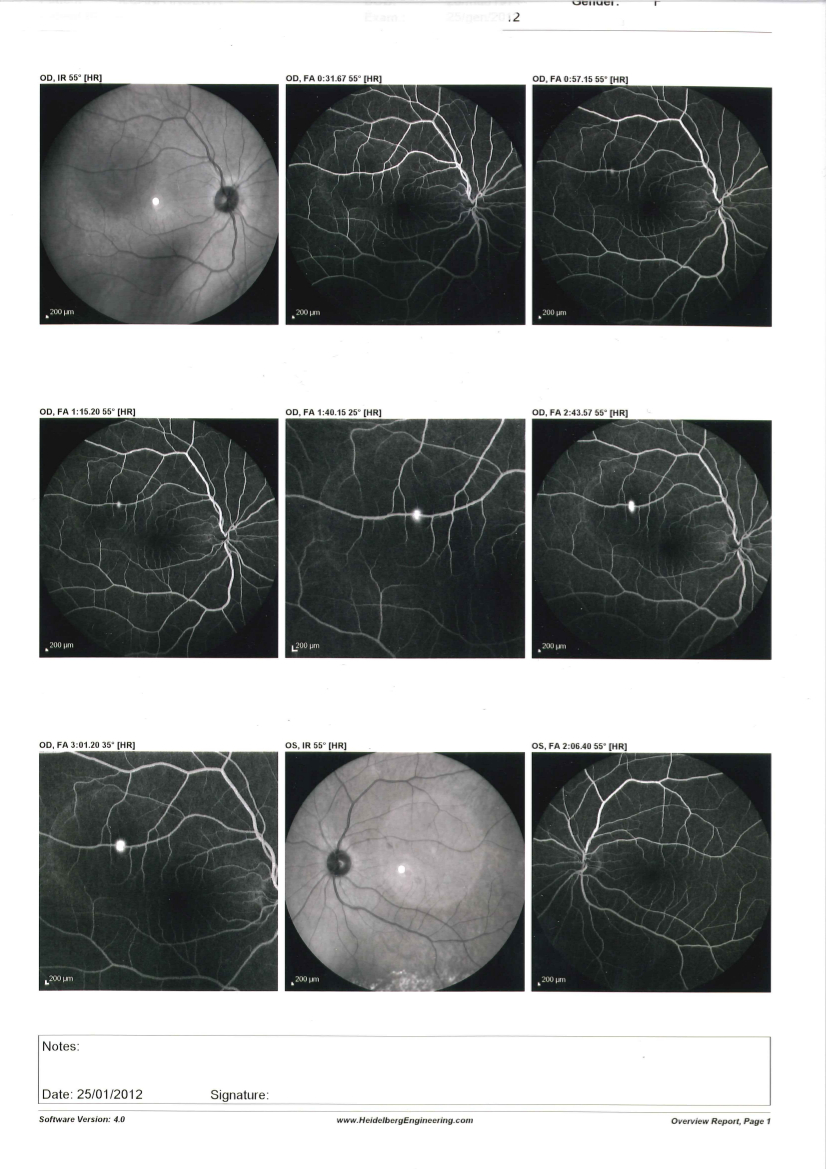

Effettuato OCT (vedi allegato): nell'occhio sinistro si evidenzia un distacco sieroso maculare

Effettuata fluorangiografia (vedi allegato): nell'occhio sinistro si evidenzia una membrana neovascolare sottoretinica maculare

Effettuata terapia con iniezioni intravitreali di farmaci anti-VEGF, la neovascolarizzazione è totalmente regredita e la paziente vede con l'occhio sinistro 10/10 con correzione ottica.

Questo caso poteva essere di difficile interpretazione all'inizio per l'assenza di emorragie retiniche maculari che indicassero la presenza di una neovascolarizzazione e per l'evidenza all'OCT di un distacco sieroso che poteva essere anche di altra natura, la fluorangiografia ha permesso di evidenziare l'esatta causa.

Questo ci dimostra come OCT e fluorangiografia siano esami entrambi importanti e con informazioni complementari e spesso è necessario effettuarli entrambi per un corretto studio delle maculopatie.